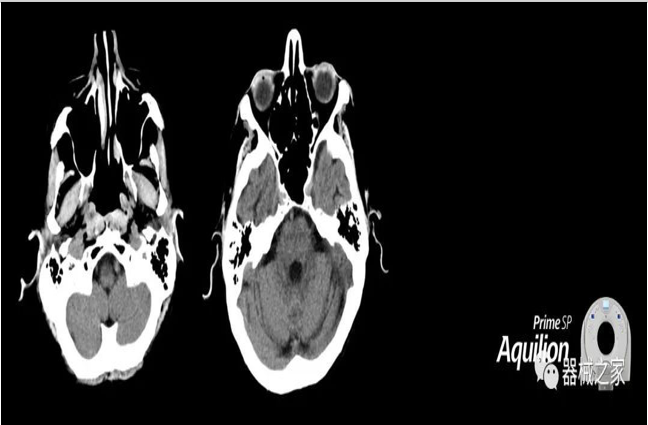

佳能醫(yī)療為Aquilion Prime,Lightning CT系統(tǒng)增加了放射治療套裝